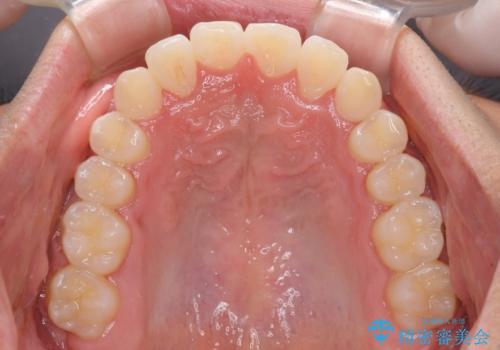

- 前歯のクロスバイトを気にして来院された患者様です。

美容専門の歯科医院を受診したところ、セラミックでの改善は無理と断られてしまったとのことでした。

歯がすり減って不揃いの形態となっていますが、まずは矯正治療によりクロスバイトを改善することとしました。